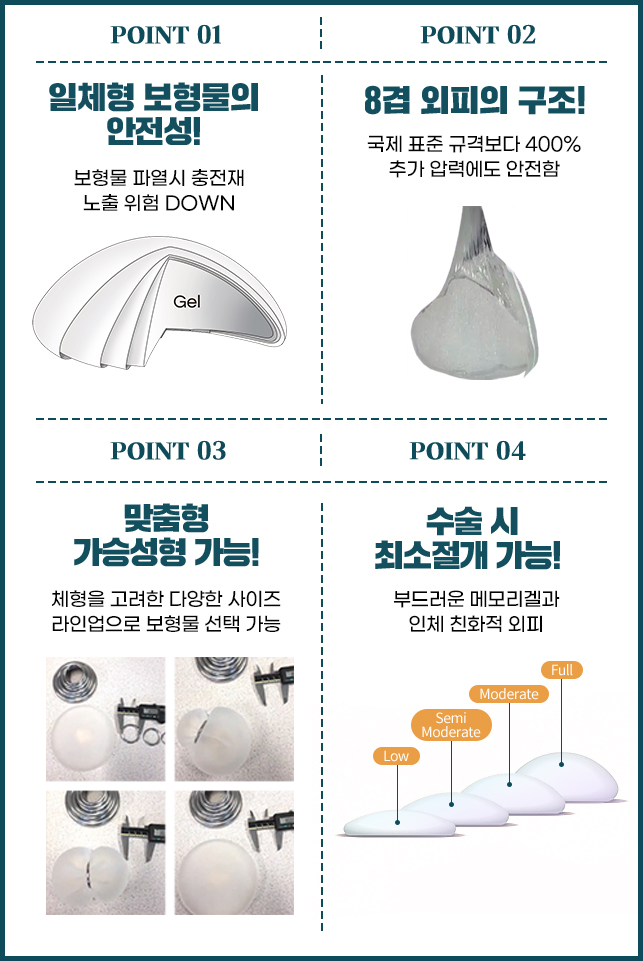

다양한 보형물 라인업

id X SEBBIN Breast Surgery

세빈 엄격한 품질관리